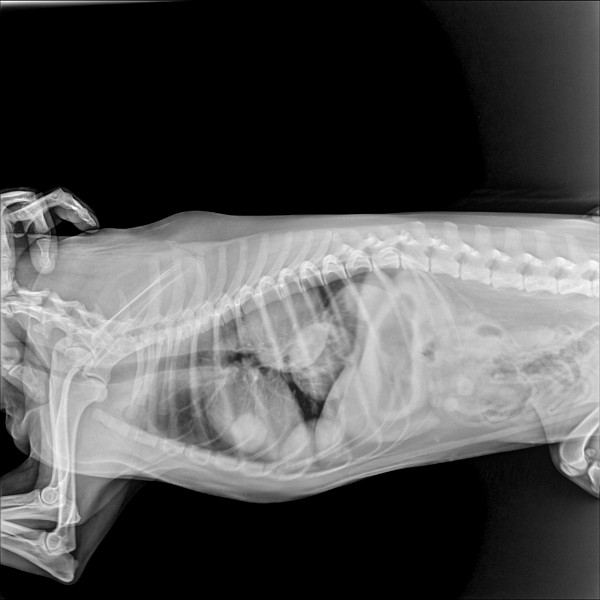

Добрый вечер! Можно ли по этим снимкам определить онкологию легких? Спасибо